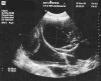

Se trata de una adolescente de 11 años, con menarquia un año antes y sin antecedentes patológicos, que acudió a valoración en el servicio de urgencias por distensión abdominal progresiva en los últimos 6 meses. En la exploración física presentaba clara distensión abdominal y era palpable una masa de localización y límites mal definidos, que ocupaba todo el abdomen. Se realizaron hemograma y bioquímica que fueron normales. En la ecografía abdominal se apreciaba una gran formación quística y multiseptada, probablemente en relación con el ovario, ocupando abdomen y pelvis (fig. 1). La determinación de marcadores tumorales mostró elevación de 125Ca de 35,51 U/ml (VR < 35 U/ml) y 19.9Ca de 68,19 U/ml (N: 0-32 U/ml). Los demás marcadores tumorales, antígeno carcinoembrionario (CEA), α-fetoproteína (α -FP) y la subunidad b de la gonadotropina coriónica humana (β -HCG) fueron normales.

Figura 1. Ecografía abdominal: gran formación quística y multiseptada, probablemente en relación con el ovario.